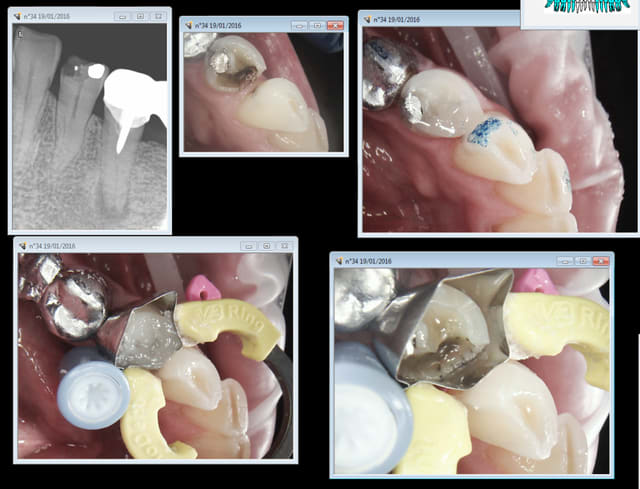

Celui ci ne m'écoute pas, ca fait des lustres que je lui dit qu'il va avoir un souci sur sa 35. La 34 à pété, aucune sensibilité à la fraise donc vraisemblablement nécrosée, ben au lieu de lui faire l'endo je lu ai fait un compo vite fait.

Pas mal l'endo sur la 45 hein ? encore un king de l'endo ! -))))

Capture d e cran 2016 01 20 10.06 - Eugenol